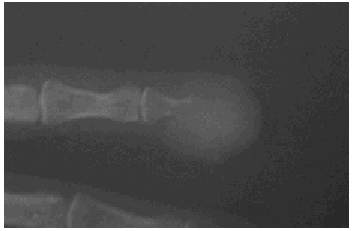

Se solicitó una radiografía de la mano izquierda en la que se observaba una lesión lítica que destruía totalmente el extremo distal de la tercera falange del segundo dedo (fig. 3). Con la sospecha clínica de lesión de origen tumoral, muy probablemente metastásica, se efectuó una biopsia cutánea del pulpejo en la que se observaba en la dermis profunda una infiltración por un carcinoma de células claras. El tumor se disponía en nidos sólidos separados por finos septos de estroma vascularizada (fig. 4), formando luces las cuales contenían abundantes hematíes, hallazgo éste muy característico de los carcinomas renales. Las células presentaban un citoplasma claro y vacuolado y núcleos vesiculosos con macronucléolos (fig. 5). Con esta histología y dados los antecedentes clinicopatológicos de la paciente, se estableció el diagnóstico de metástasis acral digital ósea por adenocarcinoma renal, con afectación cutánea secundaria.

Fig. 3.--En la radiografía se observaba una lesión lítica que destruía totalmente el extremo distal de la tercera falange del segundo dedo.